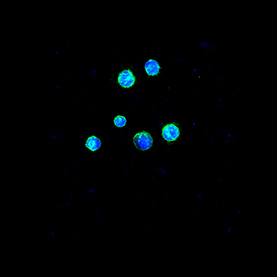

Many processes within the body are changed by the presence of cancer. These images show the response of microglia, immune defense cells in the brain, to cancer cells. When microglia encounter glioblastoma multiforme, one of the most aggressive brain cancers, they shift from a relaxed, elongated shape to a rounded, ready-for-combat conformation.

These images echo the work of Anna Atkins, a British botanist and photographer who used a contact printing technique called cyanotyping to capture the form of plants and algae. Emily Chen’s work similarly seeks to explore biological function, in this case the immune response to brain cancer, by capturing and comparing biological forms.